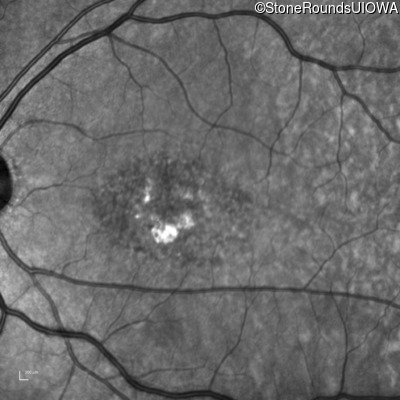

AR Stargardt Disease (IIA)

Age at visit:

53 years

OD

OS

20/200 +2

20/50 -1

AR Stargardt Disease

ABCA4

IVS40+5 G>A

Gly1961Glu GGA>GAA

AR